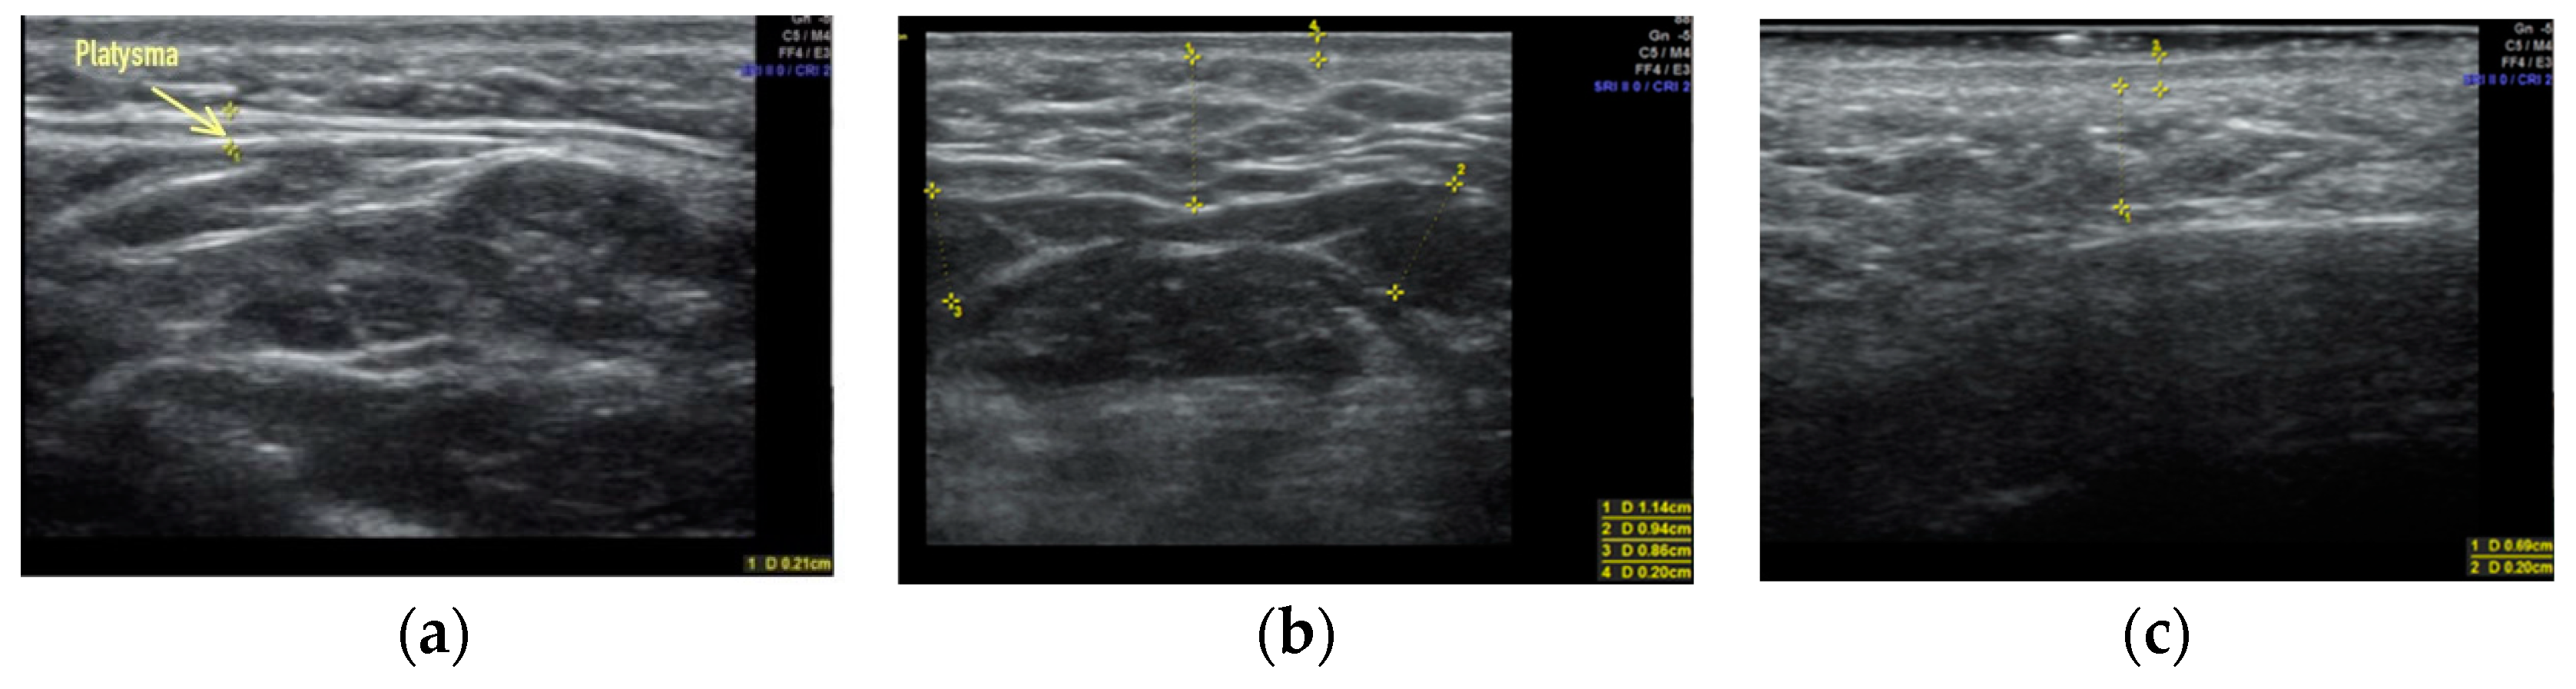

Clinical case #4. During the study, a 51-year-old male patient with a 9 MHz linear transducer of soft tissues of the lower third of the face and neck without pressure, in an upright position, showed denser platysma (diameter 2.1 mm) without signs of involutive changes (Figure 4a), and also displayed excessive accumulation of adipose tissue in the chin (Figure 4b) and along the contour of the lower jaw (Figure 4c).

Figure 4.

B-mode ultrasound examination of the soft tissues of the lower face and neck area with a 9 MHz linear transducer. Platysma (a), excessive accumulation of adipose tissue in the submandibular area (b), and along the contour of the lower jaw (c).

According to the results of the ultrasound examination, this was only enough to influence the fatty tissue in the submental area and along the contour of the lower jaw to obtain younger contours of the lower face and neck in this clinical observation.

Clinical case #5. During the study, a 48-year-old male patient with a 9 MHz linear transducer of soft tissues of the lower third of the face and neck without pressure, in an upright position, exhibited platysma (diameter 2.1 mm) without signs of involutive changes (Figure 5a) and the excessive accumulation of adipose tissue along the contour of the lower jaw from two sides (Figure 5b,c).

Figure 5.

B-mode ultrasound examination of the soft tissues of the lower third of the face and neck. A 9 MHz linear transducer. Platysma (a). Excessive accumulation of adipose tissue along the contour of the lower jaw from two sides (b,c).

Therefore, it is enough to only influence the fatty tissue along its contour to correct the contours of the lower jaw in this clinical case according to the results of ultrasound examination.

When comparing the results of the ultrasound examination of the soft tissues of the lower third of the face and neck in male (n = 14) and female (n = 73) patients, we noted that in males, involutive changes in platysma were observed at an older age than in women. It was noted that the platysma muscle itself in males (1.7 ± 0.3 mm) was thicker (0.35 ± 0.8 mm (±SE standard deviation average)) than in females, and denser (Figure 4 and Figure 5), which has a beneficial effect on its tone and prevents early ptosis of these tissues.